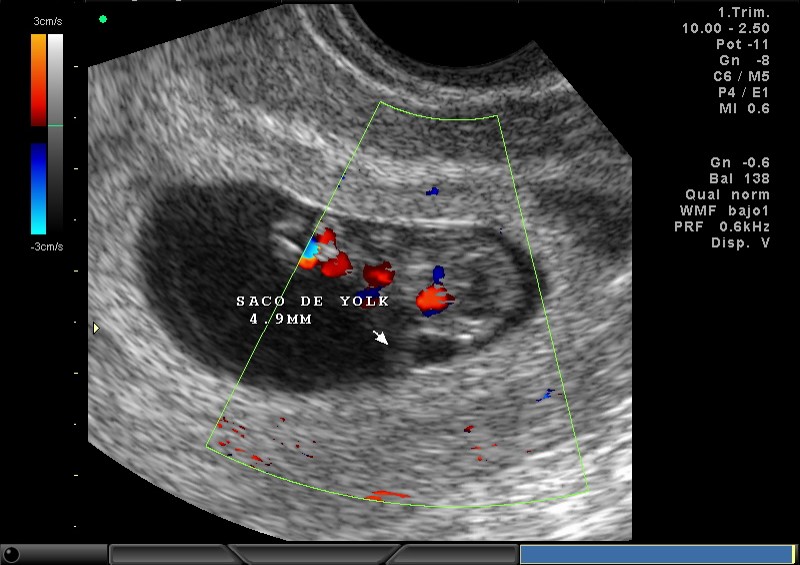

2D Y COLOR SACO AMNIOTICO, SACO DE YOLK